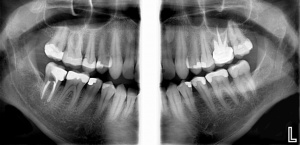

Optimizing Digital Radiography - Solving ChallengesKaren Preston MAEd, RDH, FHEA & Gordon J. Christensen, DDS, MSD, PhD Digital dental radiology has made major strides since its introduction many years ago. However, despite the obvious advantages...... |